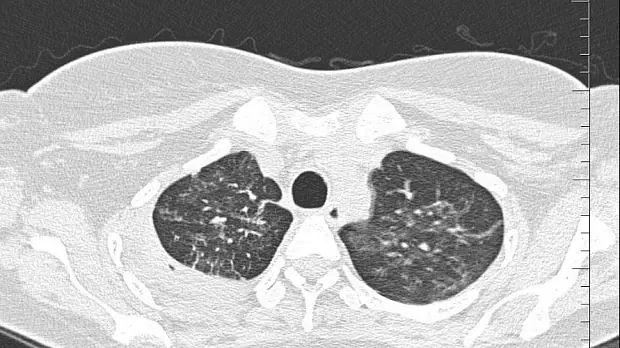

08.06.2020 проведена повторная установка блокатора в промежуточный бронх (блокатор Medlung №13) с хорошим клиническим эффектом (сброс воздуха по плевральному дренажу прекратился через 8 часов после вмешательства). Подтверждено данными Р-КТ органов грудной клетки.